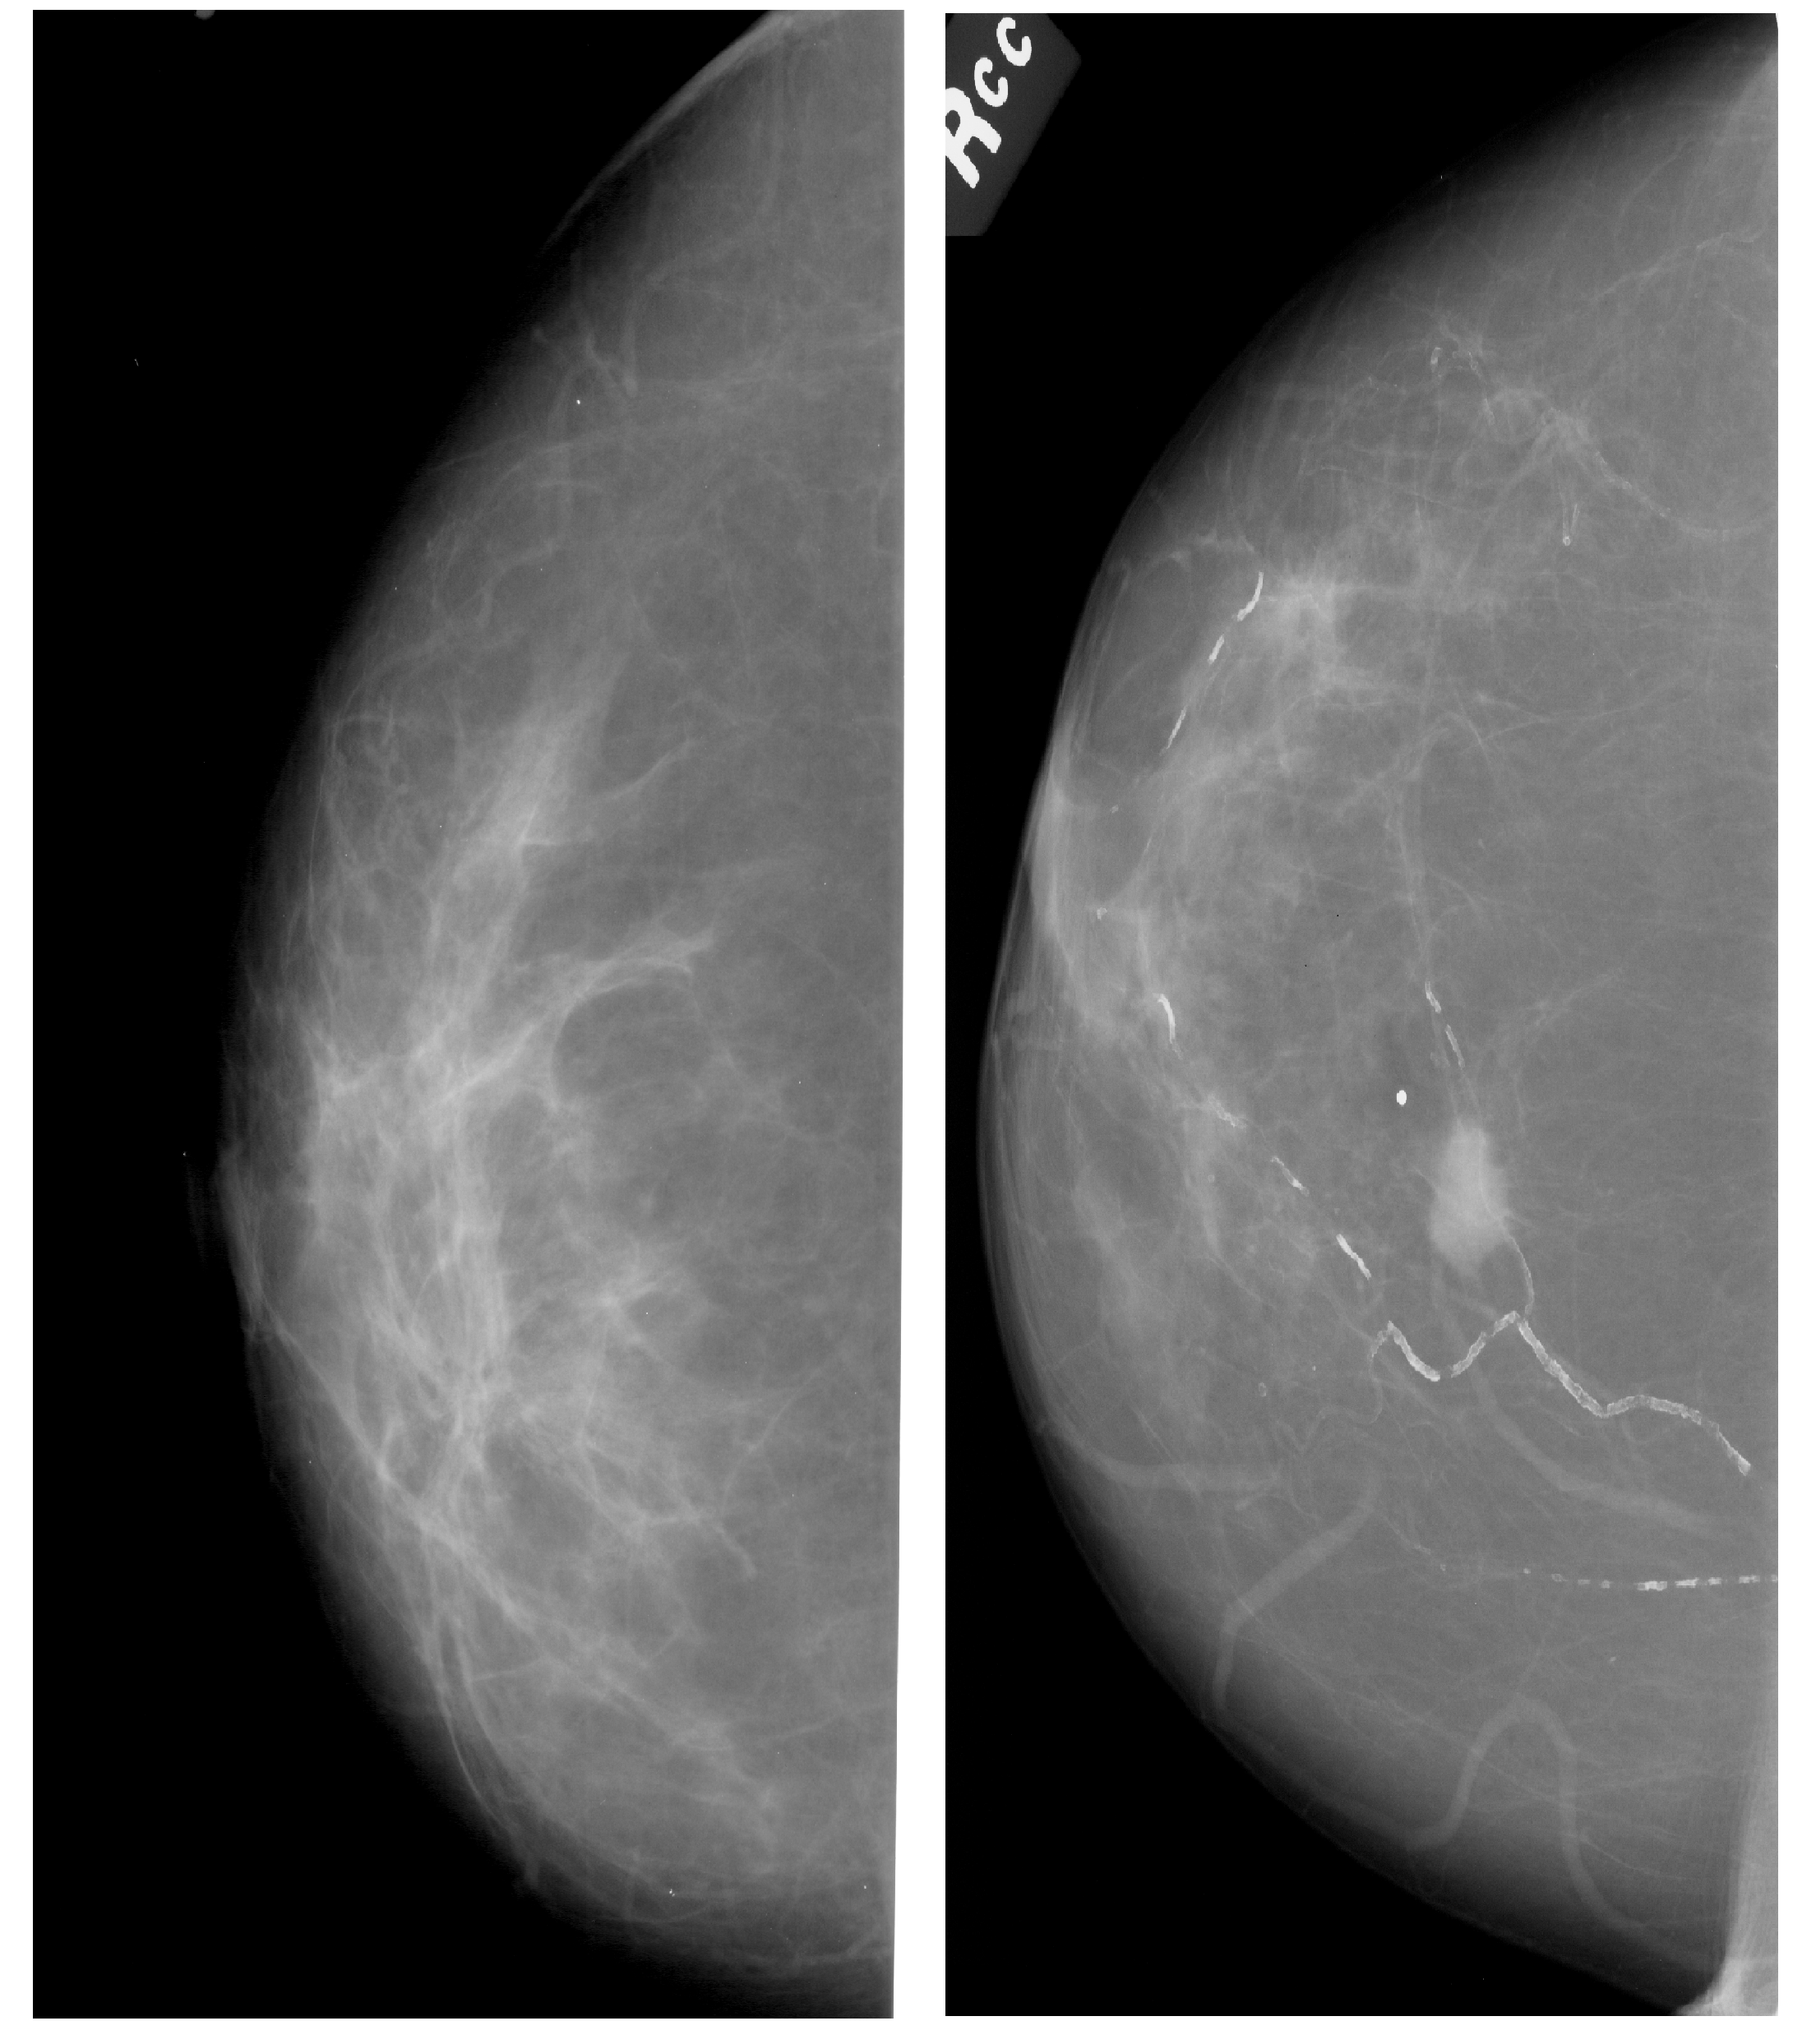

Benign (left) vs Malignant (right) tumors found in mammograms. Source: https://wiki.cancerimagingarchive.net/display/Public/CBIS-DDSM